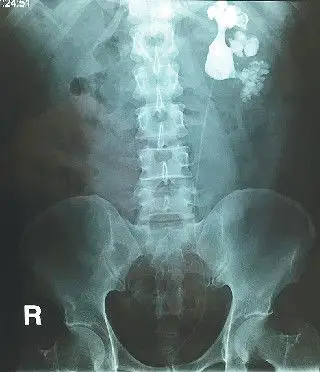

左肾结石彩超,ct检查情况2患者目前病情可考虑行经皮肾镜肾结石碎石

曾在外院行体外冲击波治疗,但效果不佳,结石非但没有排出,肾积水反而

ct影像显示肾脏被巨大结石霸占.长沙晚报通讯员 胡薇华 陈昊 供图

泌尿系统结石之肾结石ct表现

ct片上显示肾里塞满了结石

右肾结石碎石前